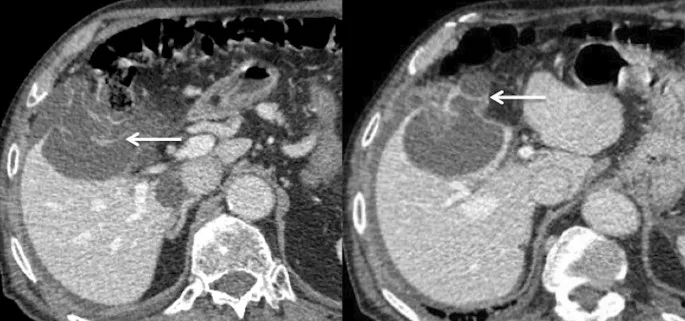

⭐ HCC Washout: Hepatocellular carcinoma (HCC) classically shows intense arterial phase hyperenhancement (APHE) followed by rapid portal venous or delayed phase "washout," appearing hypodense compared to the liver.

- Arterial Phase: Best for hypervascular lesions (e.g., HCC, FNH).

- Portal Venous Phase (~70s): Peak uniform parenchymal enhancement; most metastases appear hypodense.